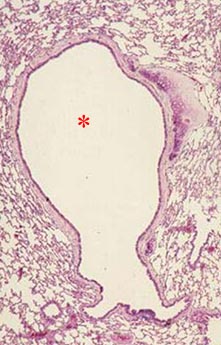

What is the structure indicated by the asterisk?

Pulmonary Bronchus (note cartilage

in upper right hand corner)